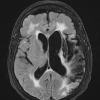

Infarct, Tract Degeneration, illustrative case (2)